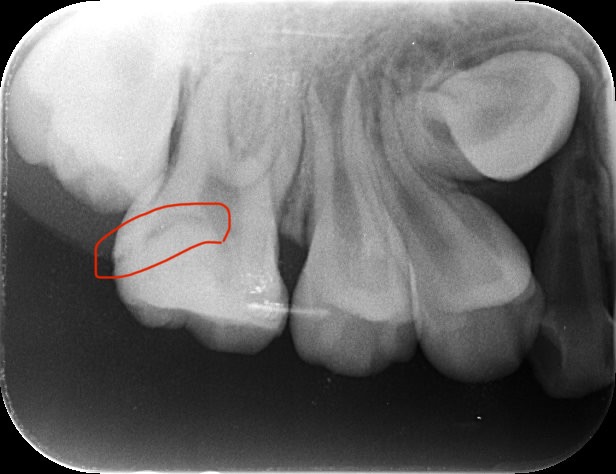

レントゲン写真、CT撮影、歯周病検査を行い、原因を調べます。

歯周病検査にて、左下奥歯の歯周ポケットの数値が8mmあり、歯周病が原因の可能性も考えられます。

また、レントゲンから確認すると、以前、歯の神経近くまで虫歯治療を受けていた可能性があります。

神経ギリギリまで虫歯が存在した場合、虫歯自体はしっかり取り切っていても、虫歯の菌がすでに神経内部に侵入してしまっている可能性があります。